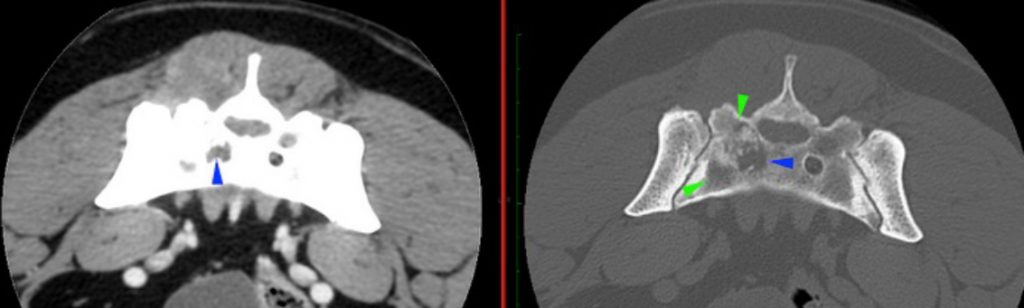

There is a well-defined, irregular to ovoid mass centred at the right caudal aspect of the sacrum (red arrowheads). It is soft tissue attenuating with mineral attenuating foci medially and showing heterogeneous strong contrast enhancement with hypoattenuating and poorly enhancing areas within. It is causing the moth-eaten lysis of the right body of the sacrum (green arrowheads) with irregular margination of the right ventral sacral foramina (blue arrowheads). There is a periosteal reaction noted dorsal to the right sacroiliac joint and ventral caudal sacral body. The mass is invading the sacral canal to this level with complete attenuation of the perineural fat at the level of the right ventral sacral foramina.